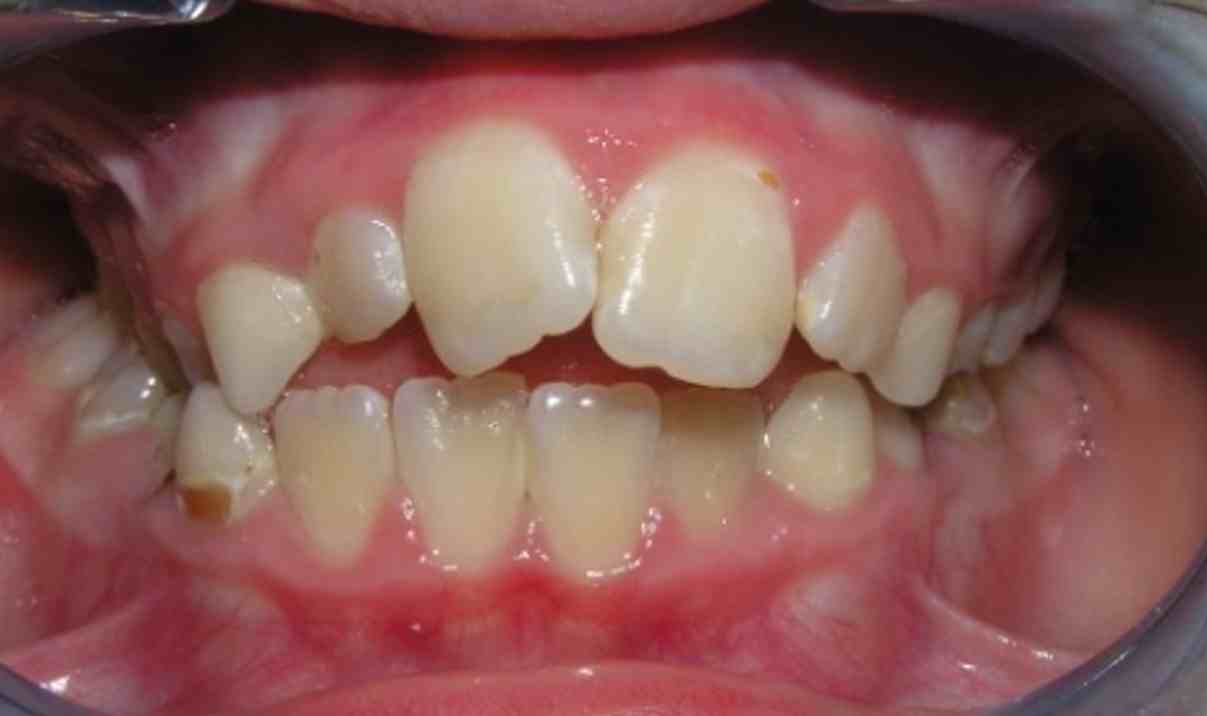

Pic.22. Tortoocclusion of teeth 11 and 21, open bite.

Pic.23. Tortoocclusion of teeth 11 and 21, prognathic, cross bite.